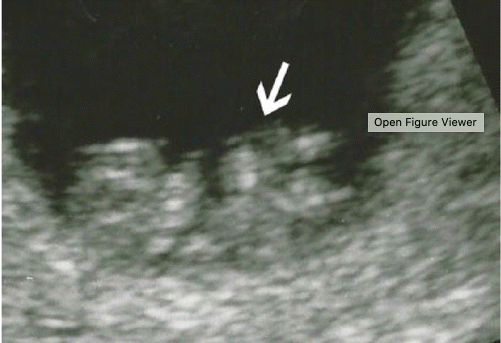

Name of this sign which is specific for Chiari II malformations?

The banana sign (red arrows).

Banana sign describes the characteristic flattened cerebellar hemispheres in

the small posterior fossa.

Very specific for Chiari II. If the banana sign is seen, then a myelomeningocele is presumed to be present even if not identified on ultrasound.

Yellow arrows point to lemon sign- scalloping of the frontal bones (not specific).